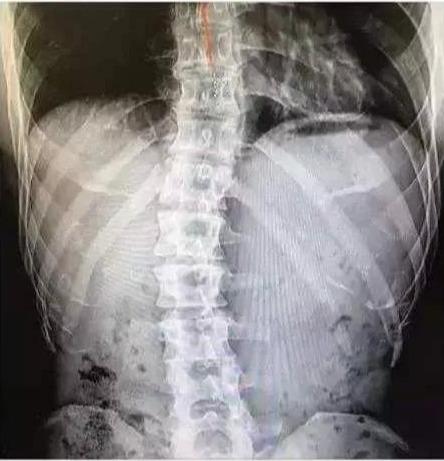

但不管怎么说 , 金钟国对健身的热爱、以及他的极度自律精神还是值得我们学习的 。 小时候的他曾经脊柱侧弯 , 很长一段时间被病痛折磨着 , 是健身让他越来越健康 , 身体也越来越好 。